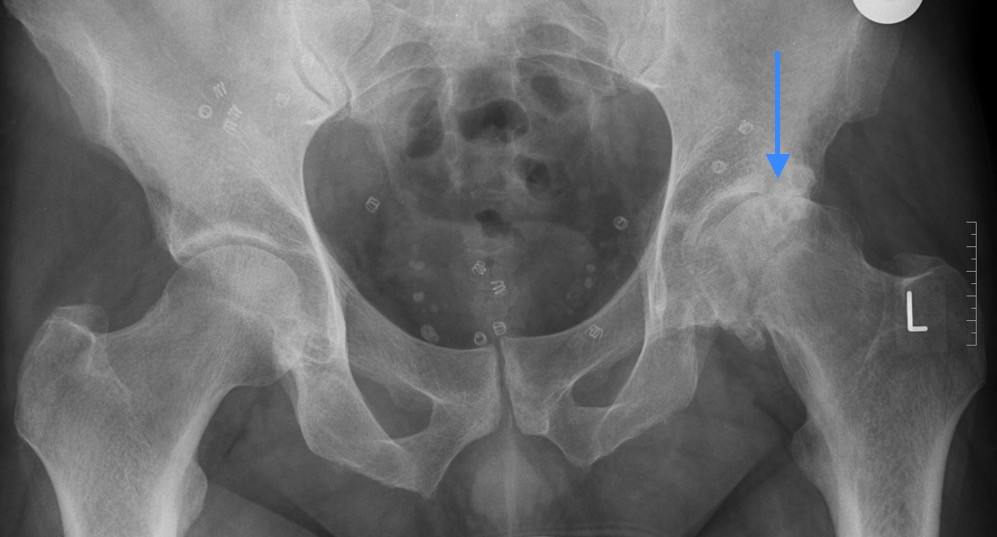

Schwere Arthrose der Linken Hüfte

Abb. 2: Schwere Arthrose der Linken Hüfte (Pfeil), während die rechte Hüfte noch normal ist.